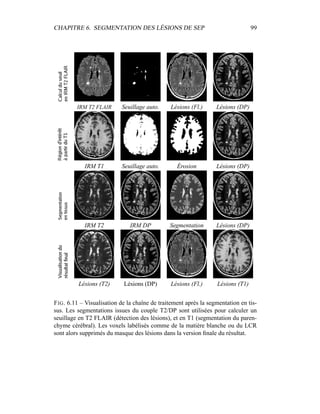

dans l’image et de prendre les intensités des voxels xi comme données1

. Après une

initiation des γk

i qui reste à définir, il suffit d’alterner les étapes de Maximisation

(équations 4.11) et d’Espérance (équation 4.10).

– Étape préliminaire : initialiser les labélisations des images (aléatoirement,

ou avec un atlas statistique)